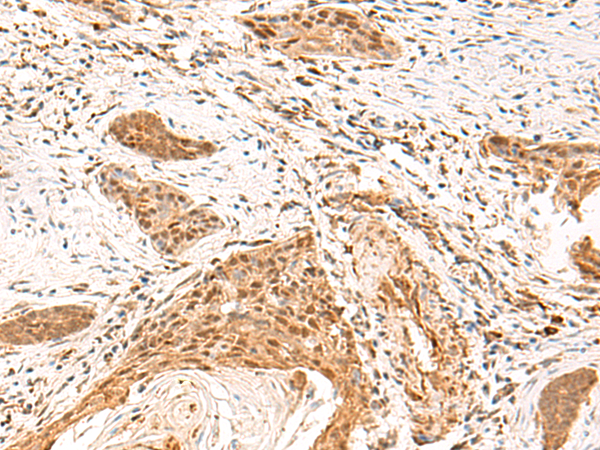

分类: 科研抗体货号: P10118别名: QA1; HLA-6.2应用: IHC反应种属: Human